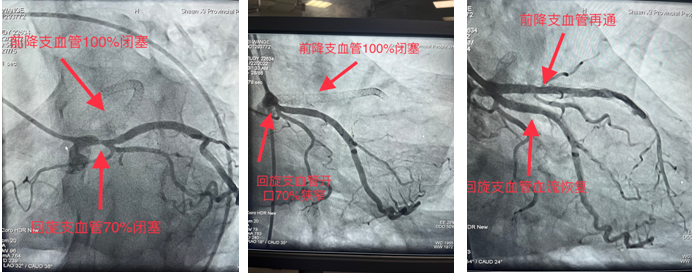

一患者月余前在外院行冠脉手术,手术未成功,遂前来21点技巧中心 求医,心血管内一科收入,并于11月22日安排冠脉手术为患者诊治病症。造影显示前降支支架内100%闭塞,回旋支开口70%狭窄。由于血管闭塞时间久,且之前支架内完全闭塞,术中出现心律缓慢、血压下降等危险因素。最终,在心血管内一科张勇主任医师、潘硕副主任医师、马彦鹏主治医师及介入放射诊疗手术室护师郭朝望、技师吴华楠等的默契配合和共同努力下,陈旧性冠状动脉闭塞血管得以再通,心脏血流恢复,生命体征随之好转,手术顺利完成。